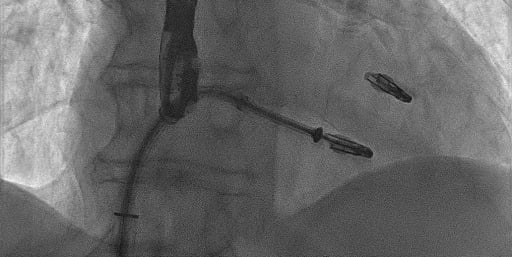

ANGIOPLASTICA

Angioplastica coronarica e lo stent

Si tratta del piu' comune trattamento attualmente utilizzato per curare l'aterosclerosi coronarica. E' una metodica che si avvale di molteplici strumenti appositamente ideati e realizzati e puo' essere effettuata subito dopo la coronarografia, utilizzando la stessa via di accesso arterioso. Solitamente, il paziente sottoposto ad angioplastica coronarica programmata puo' essere dimesso il giorno successivo alla procedura. Lo stent coronarico e' un dispositivo di grandezza millimetrica, in lega metallica biocompatibile (quindi senza fenomeni di rigetto), che viene utilizzato di solito dopo la dilatazione dell'arteria coronarica con il palloncino, per mantenere la pervietà della arteria.